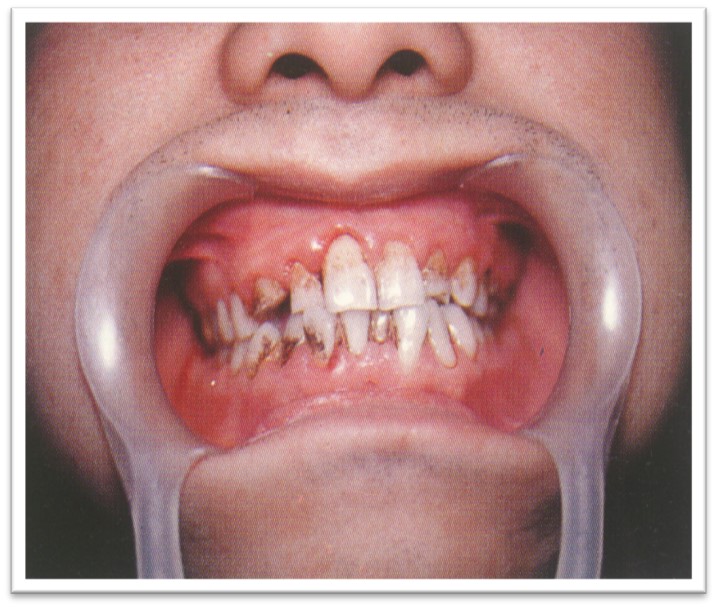

多与青春期、女性经期、妊娠或药物使用等过程密切相关,可逐渐恢复、消退或逆转。

常表现为龈乳头增大(图10.1-3)。

图10.1-3 龈增生